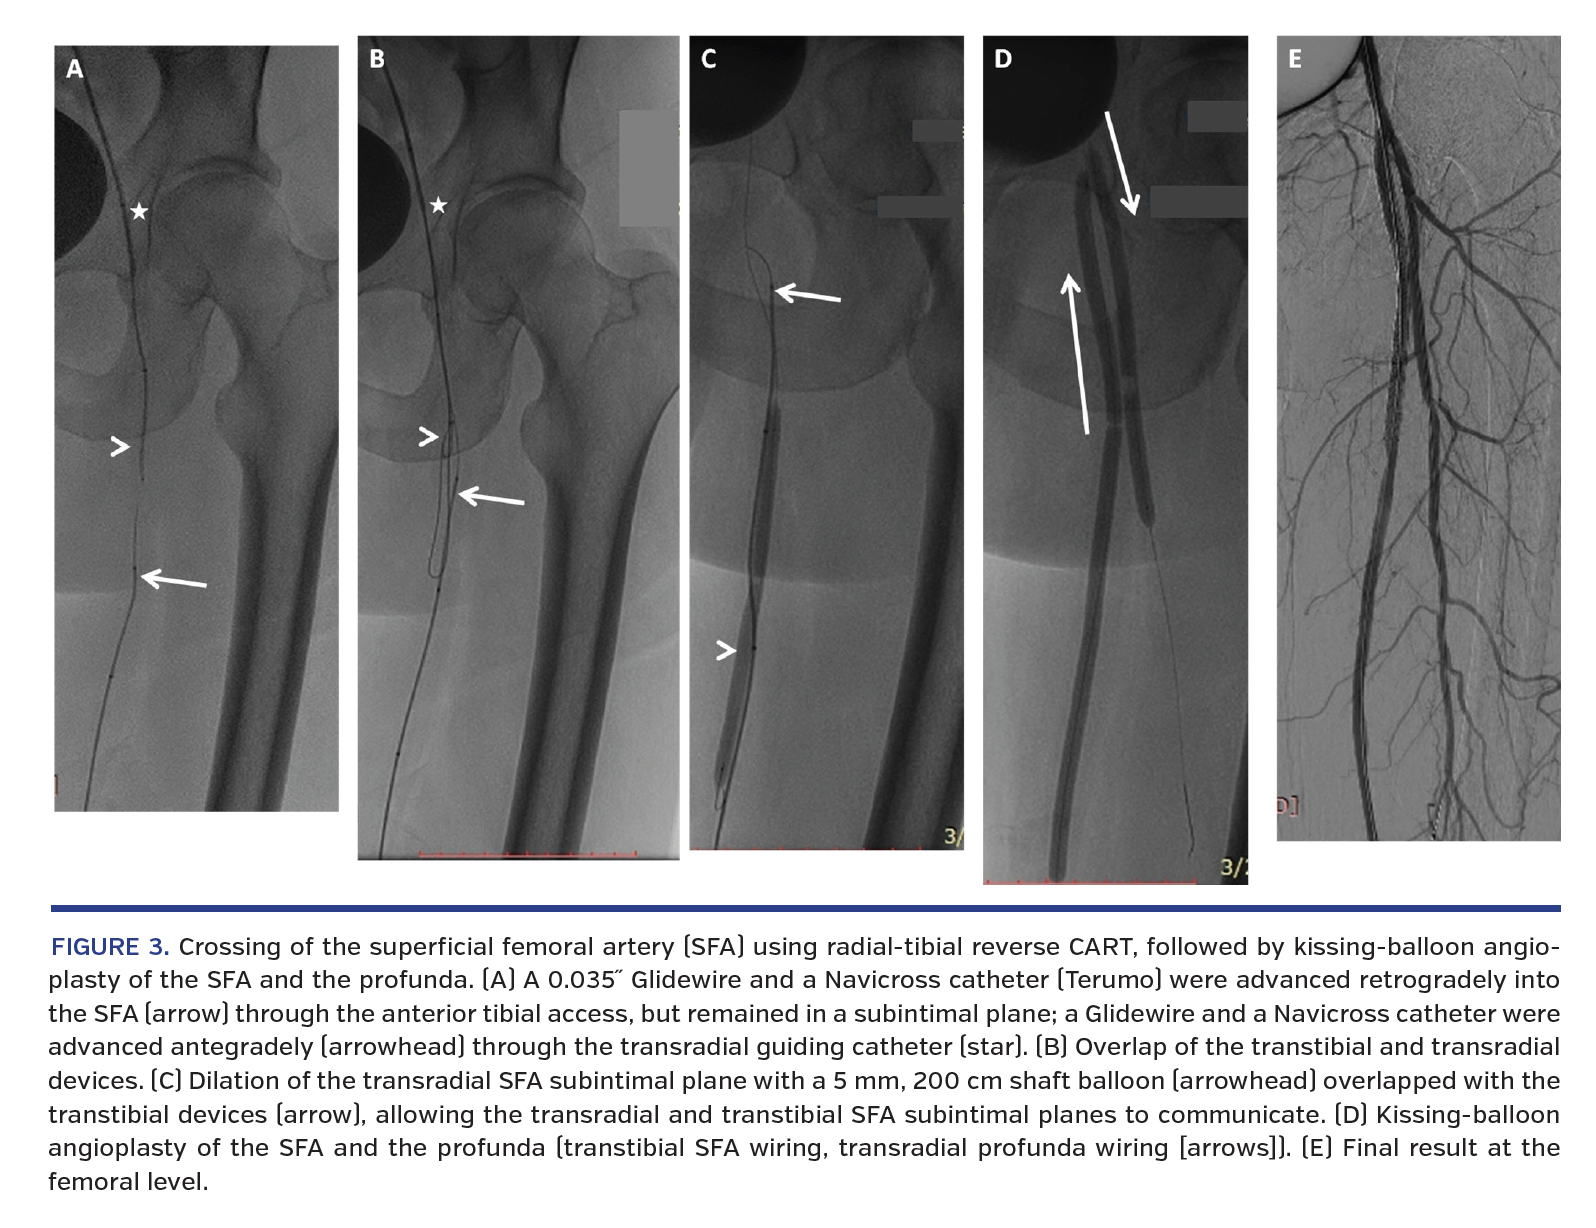

4. After infrapopliteal therapy, the superficial femoral artery (SFA) was retrogradely crossed transtibially using a 0.035˝ catheter and a 0.035˝ guidewire. The latter devices went subintimally at the level of the proximal SFA.

5. In order to allow retrograde femoral re-entry, additional 0.035˝ devices were advanced into the SFA antegradely through the transradial guiding catheter, attempting to create a radial-tibial rendezvous (Figures 3A, 3B). The subintimal SFA was then dilated antegradely using a 5 x 100 mm, 200 cm shaft monorail balloon (radial-tibial reverse controlled antegrade-retrograde tracking [CART]) (Figure 3C). This allowed re-entry of the retrograde devices into the true lumen of the common femoral artery.

6. The SFA was subsequently dilated through the AT access, and the profunda was wired and simultaneously dilated through the radial access (radial-tibial kiss) (Figures 3D, 3E). The SFA ostium was eventually stented through the AT access, and accurate stent positioning was ensured using transradial roadmap imaging.